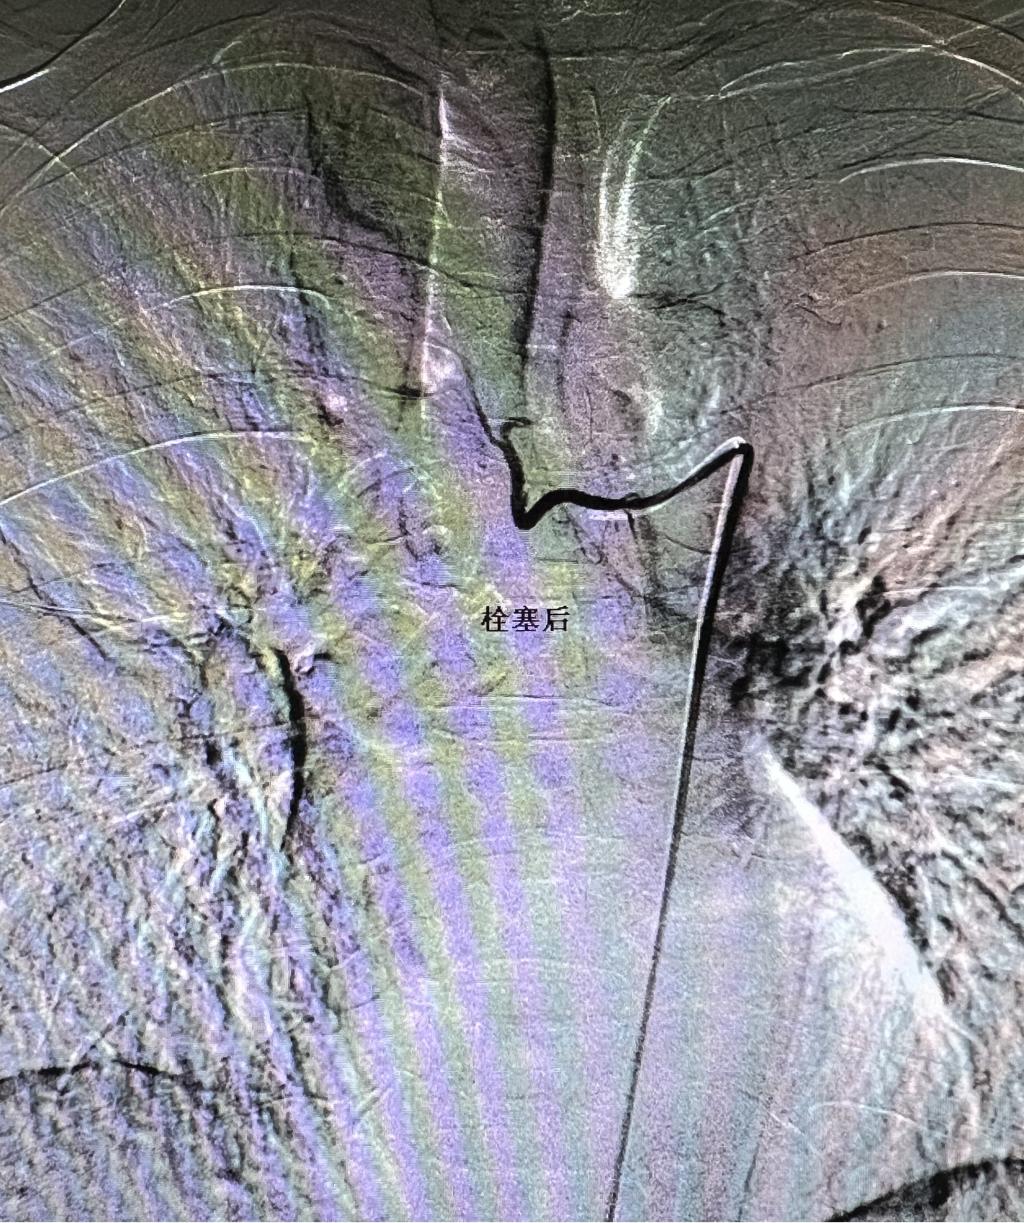

患者刘某,女性,75岁,结核咯血保守治疗十余天后突发大咯血,介入科会诊后急诊行经皮支气管动脉造影并出血动脉栓塞术。正值午饭时间,但一期二期手术室均有平诊患者,介入科主任李建国立即协调临床相关科室停止平诊手术,争分夺秒确保绿色通道危急重患者第一时间得到救治。护士长白小爱组织护理团队对术室消杀、积极术前准备。副主任何彤迅速通过支气管动脉造影确认出血动脉,历经数十分钟紧张有序的精准栓塞,原出血立止,患者转危为安。